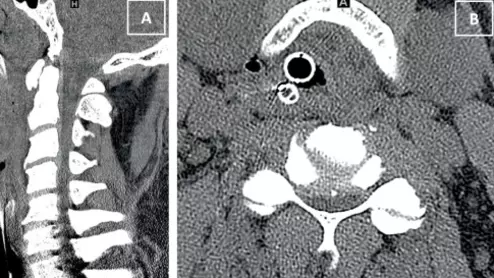

spinal cord injury on CT of patient with degenerative spinal changes

This is increasingly recognized as a potentially underreported phenomenon, accounting for roughly half of all such injuries in certain populations.